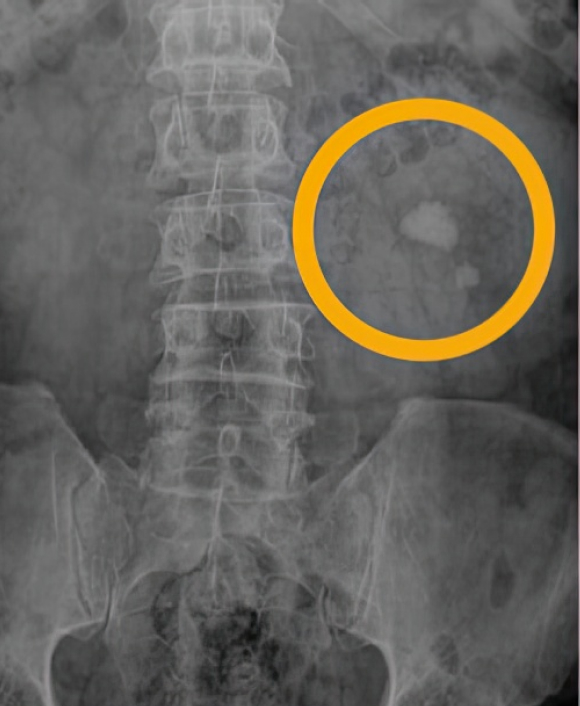

요로결석 환자의

신장요관방광단순촬영(KUB)